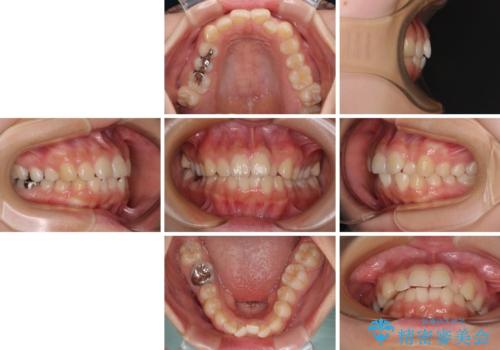

【モニター】デコボコとクロスバイトの前歯 ワイヤー装置での抜歯矯正

- 20代女性

- 矯正装置

- メタルブラケット

- 治療計画

- 前歯のクロスバイトと口元の膨らんだ横顔の印象を気にして来院された患者様です。

レントゲン写真の分析結果からは、それほど口元が突出しているという結果にはなりませんでした。

しかしながら、唇を閉じたときに口元に緊張感があり、そのまま叢生を解消すると横顔が突出した印象になる可能性が高かったため、上下左右の小臼歯4本を抜歯して、ワイヤー装置にて矯正治療を行うこととしました。

矯正治療後には、目立っていた奥歯の銀歯をオールセラミッククラウンへ作り替え、スッキリした口元に仕上がりました。